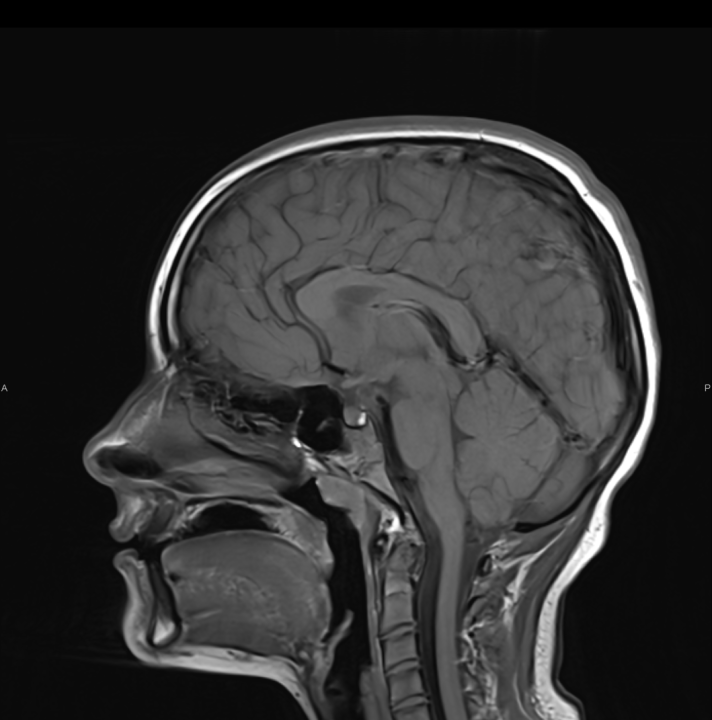

Naručite se na rendgen, ultrazvuk, CT ili MR u Poliklinici Affidea Vita

Ako su vam potrebni specijalistički pregledi mamografija, RTG, UZV, CT i MR, koji se inače koriste za dijagnostiku velikog broja zdravstvenih problema, možete ih obaviti već danas ili sutra.